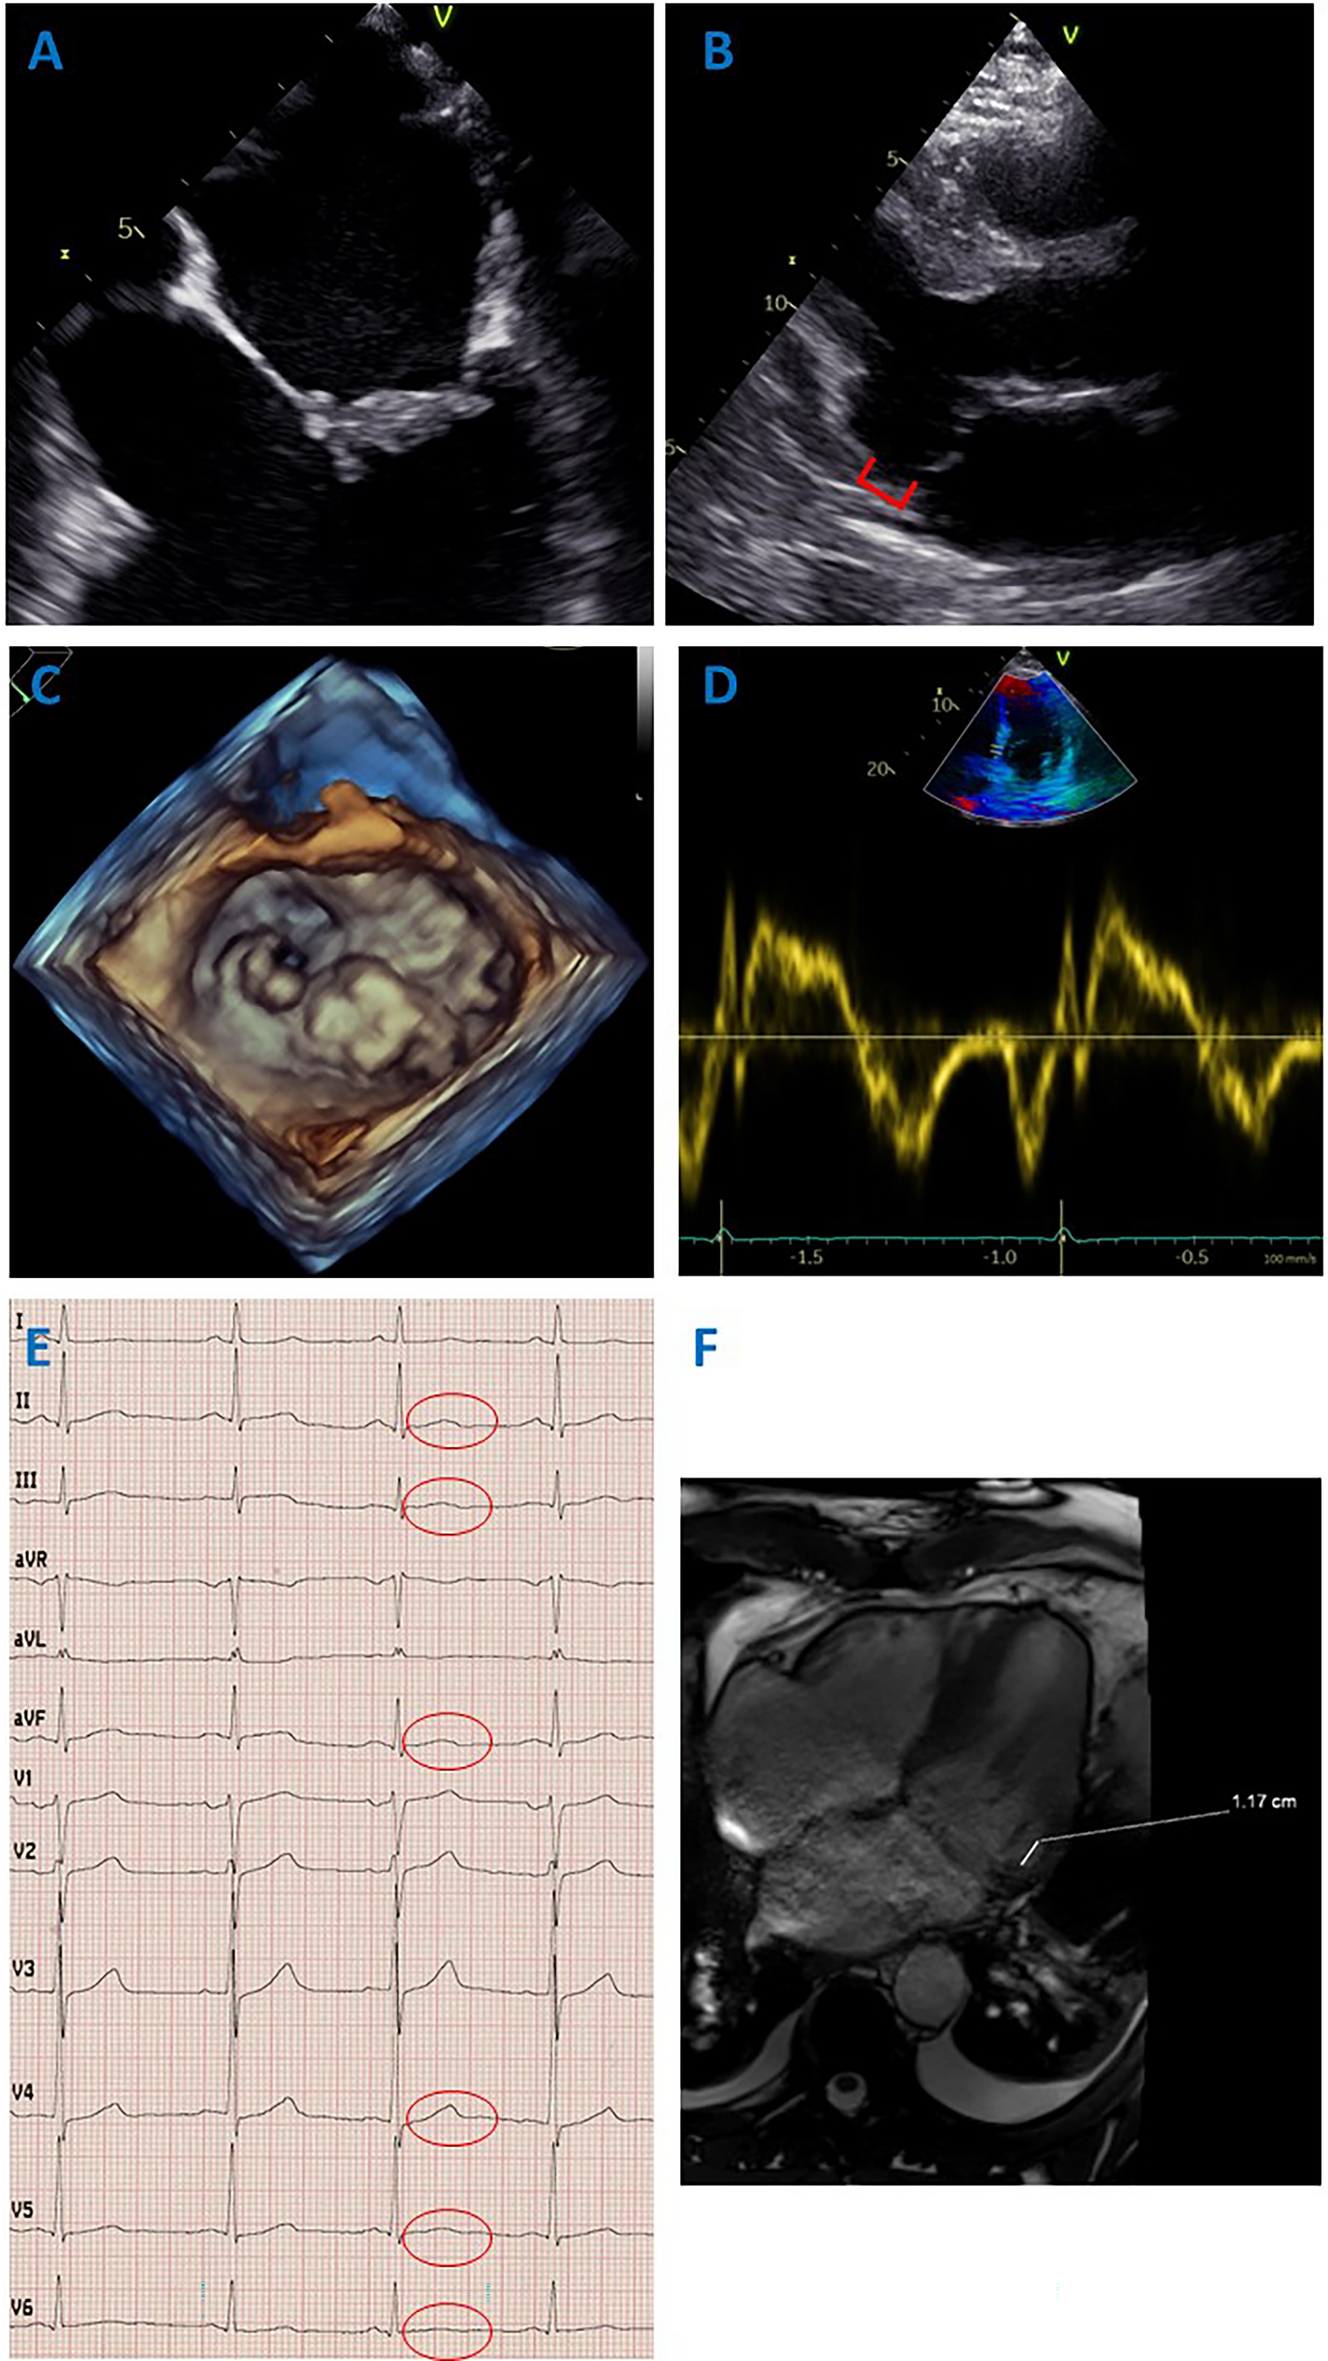

Physical examination revealed a 4/6 noisy systolic murmur with punctum maximum over the mitral valve. The ECG demonstrated subtle biphasic T waves in the inferior leads and leads V4–V6 (Fig. 1E). Initially, there were no laboratory abnormalities, especially no cardiac troponin elevations, electrolyte disturbances, or abnormal thyroid-stimulating hormone levels. Coronary angiography did not reveal any stenoses of the coronary vessels, so that acute coronary syndrome could be excluded. CT thorax and CT angiography revealed no evidence of aortic dissection or pulmonary artery embolism. By cranial CT, intracranial hemorrhage as a cause of cardiovascular arrest has been ruled out. Cardiac MRI revealed no evidence of myocarditis or other myocardial disease. Transthoracic echocardiography demonstrated severe central mitral regurgitation in a normal sized left ventricle with good systolic pump function without regional wall motion abnormalities. Left atrial volume was slightly increased (96 mL), the left ventricular end-systolic diameter was 43 mm. Vena contracta width was 9 mm, whereas regurgitant volume was 67 mL/beat and effective regurgitant orifice area was 47 mm2. Furthermore, mitral annular disjunction (12 mm) was evident (Fig. 1B). Transesophageal echocardiography revealed findings of bileaflet mitral valve prolapse (MVP) with markedly thickened valve leaflets, particularly with predominance on the posterior leaflet (Fig. 1A, C).

Fig. 1

Demonstrating the clinical findings in this patient. A Thickening of the mitral valve leaflets, primarily with accentuation of the posterior leaflet. B Mitral annular disjunction on transthoracic echocardiography. Mitral annular disjunction is defined as systolic separation between the ventricular myocardium and the mitral annulus supporting the posterior mitral leaflet. C Bileaflet mitral valve prolapse on 3-dimensional echocardiography. D Tissue Doppler showing no Pickelhaube sign. E 12-lead ECG showing subtle biphasic T waves in the inferior leads and leads V4–V6. F Cardiac MRI demonstrating a mitral annular disjunction of 11.7 mm

Electrocardiographic features of arrhythmic MVP syndrome may include inverted or biphasic T waves, especially in the inferior and lateral leads [9]. This was also present in our patient (Fig. 1E). In addition, QT prolongations, fragmented QRS complexes, or premature ventricular contractions, have been reported in other cases of arrhythmic MVP syndrome, but were not apparent in the patient [4].

Furthermore, an increased risk of ventricular arrhythmias in the presence of a bileaflet MVP on echocardiography has been described before [4, 9]. Moreover, the risk of sudden cardiac death increases with the severity of mitral regurgitation [10]. The patient had involvement of both valve leaflets as well as severe mitral regurgitation (Fig. 1A, C). Another strong risk factor for the presence of arrhythmic MVP syndrome is mitral annular disjunction, which is characterized as systolic separation between the ventricular myocardium and the mitral annulus supporting the posterior mitral leaflet [4, 11]. A further phenomenon associated with arrhythmic MVP syndrome is mitral annulus curling, which is defined as an unusual systolic movement of the posterior mitral annulus toward the adjacent myocardium [4]. Mitral annular disjunction, but not mitral annulus curling, was also detected echocardiographically in our patient (Fig. 1B).

The Pickelhaube sign is a spiked tissue Doppler velocity profile that is also associated with arrhythmic MVP syndrome [12]. This could not be demonstrated in our patient (Fig. 1D).

In addition, cardiac MRI may be helpful in establishing the diagnosis, since an association of late gadolinium enhancement in the papillary muscle region or patchy myocardial fibrosis in the left ventricular infero-basal region with the occurrence of ventricular arrhythmias has been described [13]. However, cardiac MRI was unremarkable in this patient except for the detection of mitral annular disjunction of 11.7 mm (Fig. 1F).